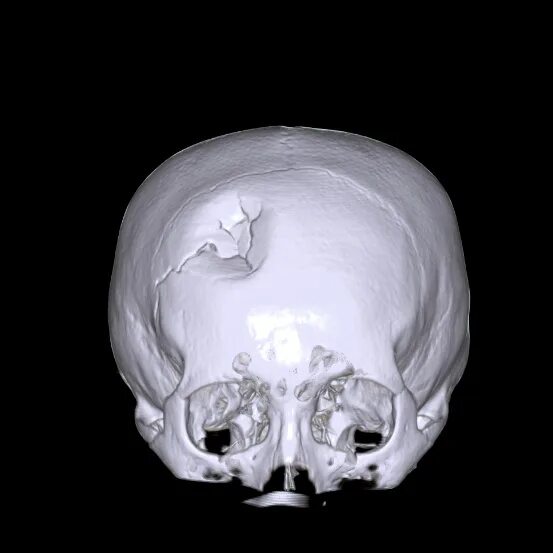

Череп на кт